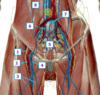

What view of the femur is this?

Posterior view

(You can see the intercondylar notch in between the medial and lateral condyles)

Fig. 56.2 Adapted from Gilroy et al. Atlas of Anatomy, 2nd edition, Figs. 26.4 A, 26.4 B

Which structure is labeled by #2?

Inguinal ligament

Which structures are in group A?

Superficial femoral artery, and vein

Femoral nerve

Which structure is labeled by #3?

Femoral artery and femoral vein

Fig. 59.7 Adapted from Gilroy et al. Atlas of Anatomy, second edition, Fig. 29.34 B.